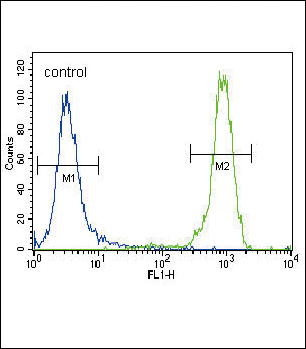

Ki67, Monoclonal Antibody (Cat# AAA19350)